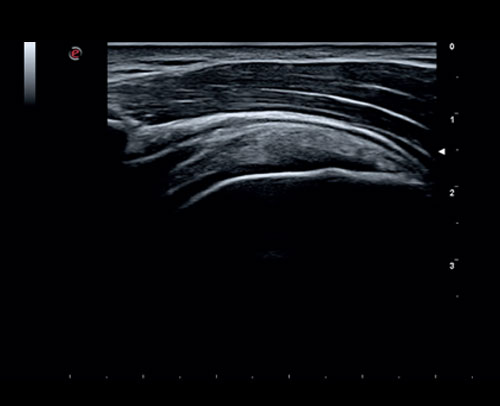

MSK zobrazení ramene